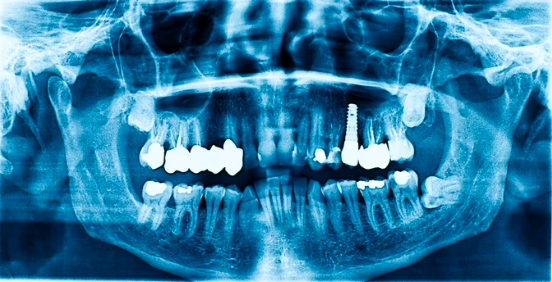

1. カウンセリング・精密検査(CT撮影など)

骨が少ない場合でも対応できることがあります

オールオン4では、

骨のある部分を選んでインプラントを埋入する設計を行います。

そのため、

「骨が足りないからインプラントは無理」と言われた方でも、

治療が可能なケースがあります。